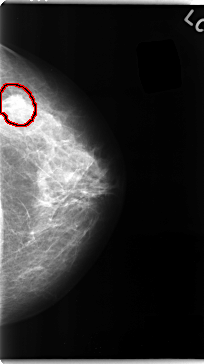

C_0097_1.RIGHT_MLO

FILE: C_0097_1.LEFT_MLO.OVERLAY

TOTAL_ABNORMALITIES 1

ABNORMALITY 1

LESION_TYPE MASS SHAPE IRREGULAR MARGINS SPICULATED

ASSESSMENT 5

SUBTLETY 5

PATHOLOGY MALIGNANT

TOTAL_OUTLINES 1

BOUNDARY